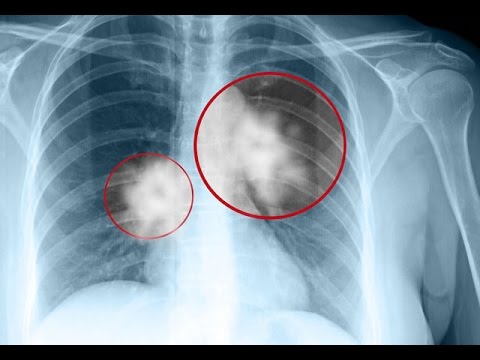

Dünyada ve ülkemizde hızla yaygınlaşan akciğer kanseri erkeklerde prostat, kadınlarda ise meme kanserinden sonra en sık görülen ikinci kanser türü olarak tanımlanıyor. En korkutucu kanser türleri arasında ilk sıralarda yer alan bu kanserin belirtileri.

Hem erkeklerde hem de kadınlarda en sık ö/lüm nedeni olan akciğer kanseri sinsi bir şekilde ilerleyerek çoğu zaman hiçbir belirti vermemektedir. Bir çok kişi akciğer kanseri olduğunu, başka bir hastalık sebebiyle akciğer röntgeni çektirdiğinde öğrenmektedir.